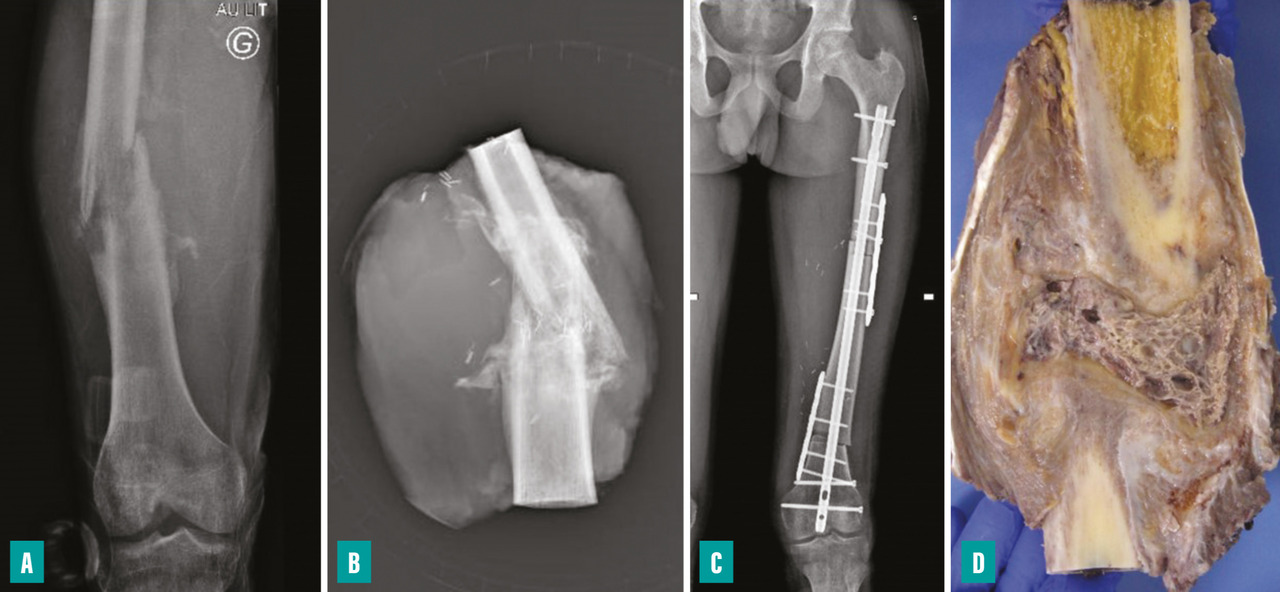

Pour les sarcomes des membres, la préservation de la fonction articulaire est le facteur déterminant. Dans la mesure du possible, les chirurgies avec préservation épiphysaire doivent être privilégiées (fig. 1). En cas d’atteinte épiphysaire, le choix de la technique opératoire dépend de la présence ou non d’un envahissement intra-articulaire, qui nécessite alors de recourir à une résection dite «  extra-articulaire  », techniquement plus exigeante (fig. 2). L’imagerie par résonance magnétique (IRM) a une place de choix pour identifier cette contamination articulaire.

La survenue d’une fracture pathologique rend plus difficile l’obtention de marges saines du fait de la dissémination de l’hématome dans les tissus mous. Elle ne semble pas augmenter le risque de récidive locale – à la condition d’obtenir des marges saines – et ne constitue donc pas une indication d’amputation (fig. 3). Lorsqu’elle survient en cours de traitement, elle fait craindre une mauvaise réponse à la chimiothérapie, qui pourrait expliquer le moins bon pronostic de ces patients.3,4